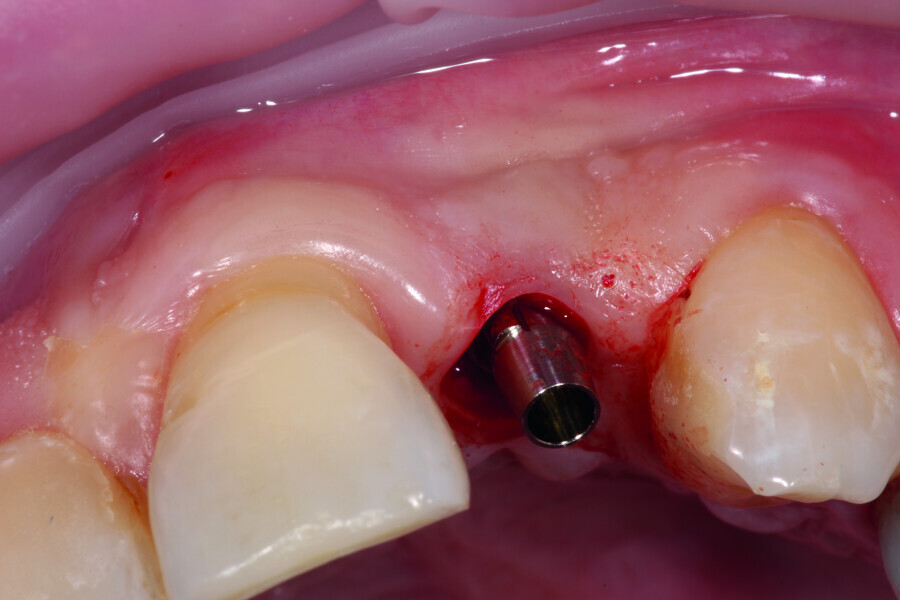

Digitising your implant practice